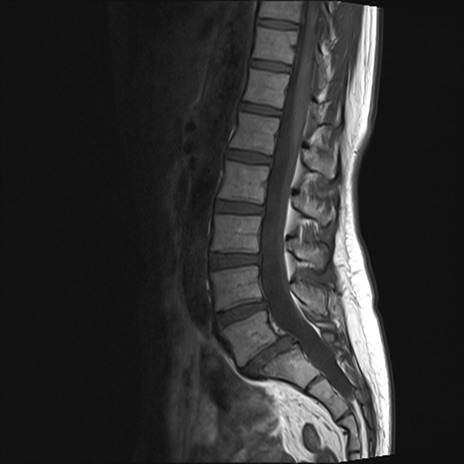

【整形】TIPS症例4 腰椎MRI T1WI(矢状断像)

腰椎MRI

T2WI(矢状断像)